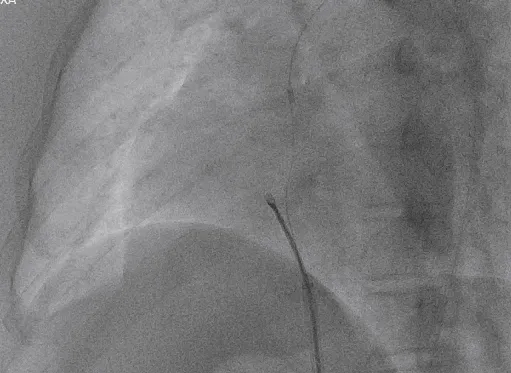

锁定后评估

释放前瓣上造影

分流明显减少

牵拉试验

牵拉试验确认封堵器稳定

释放后评估

封堵器形态良好,基本无残余分流